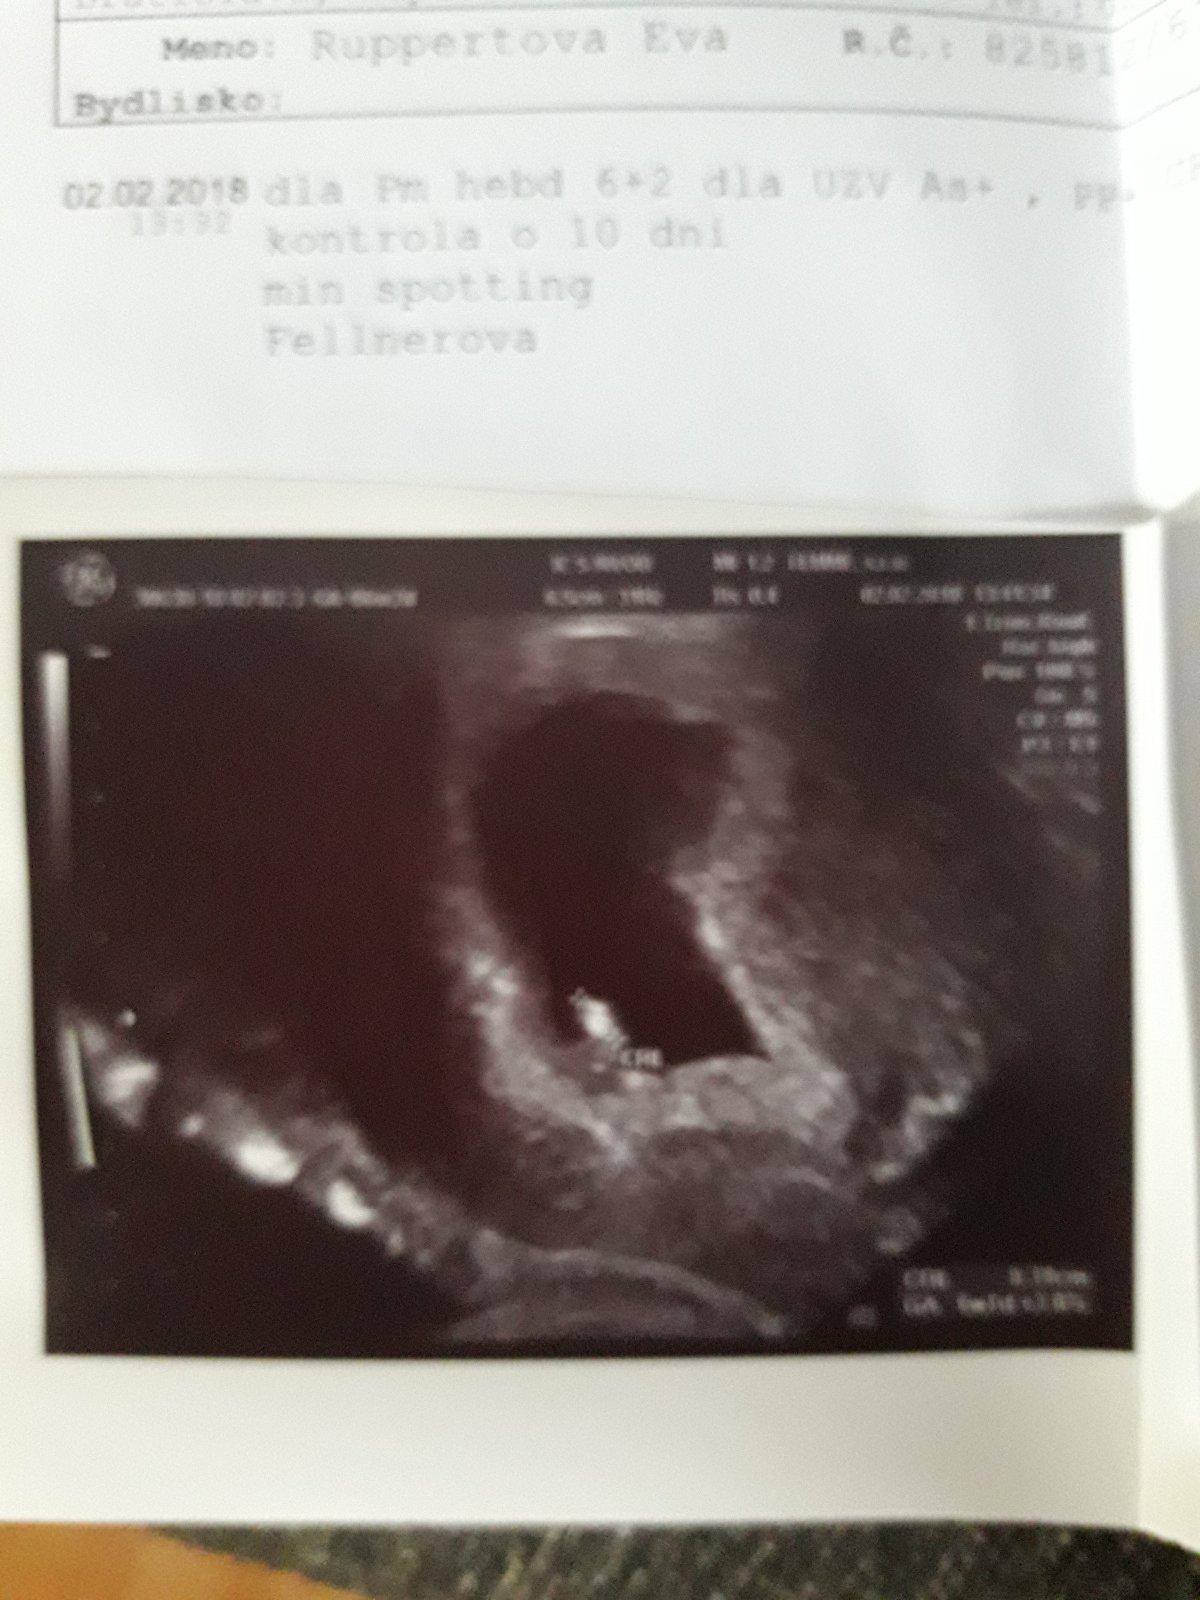

chodila tu este jedna babenka ktora mala na zaciatku problem s krvacanim... ale babatko sa drzalo zubani nechtami...len uz si nepamatam ci uz porodila ci este nie...nick tusim zacinal na b a tusim v nom bolo aj nejake cislo....